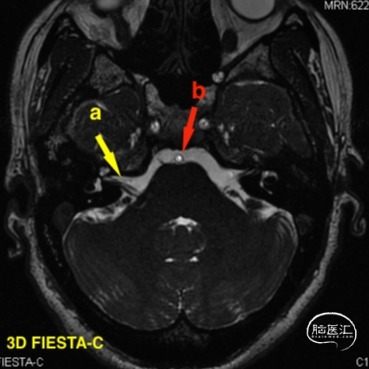

头颅MR(2021-07-23),面听神经复合体未见明显血管压迫。

a 黄色箭头为患侧面听神经复合体 b 红色箭头为动脉成像